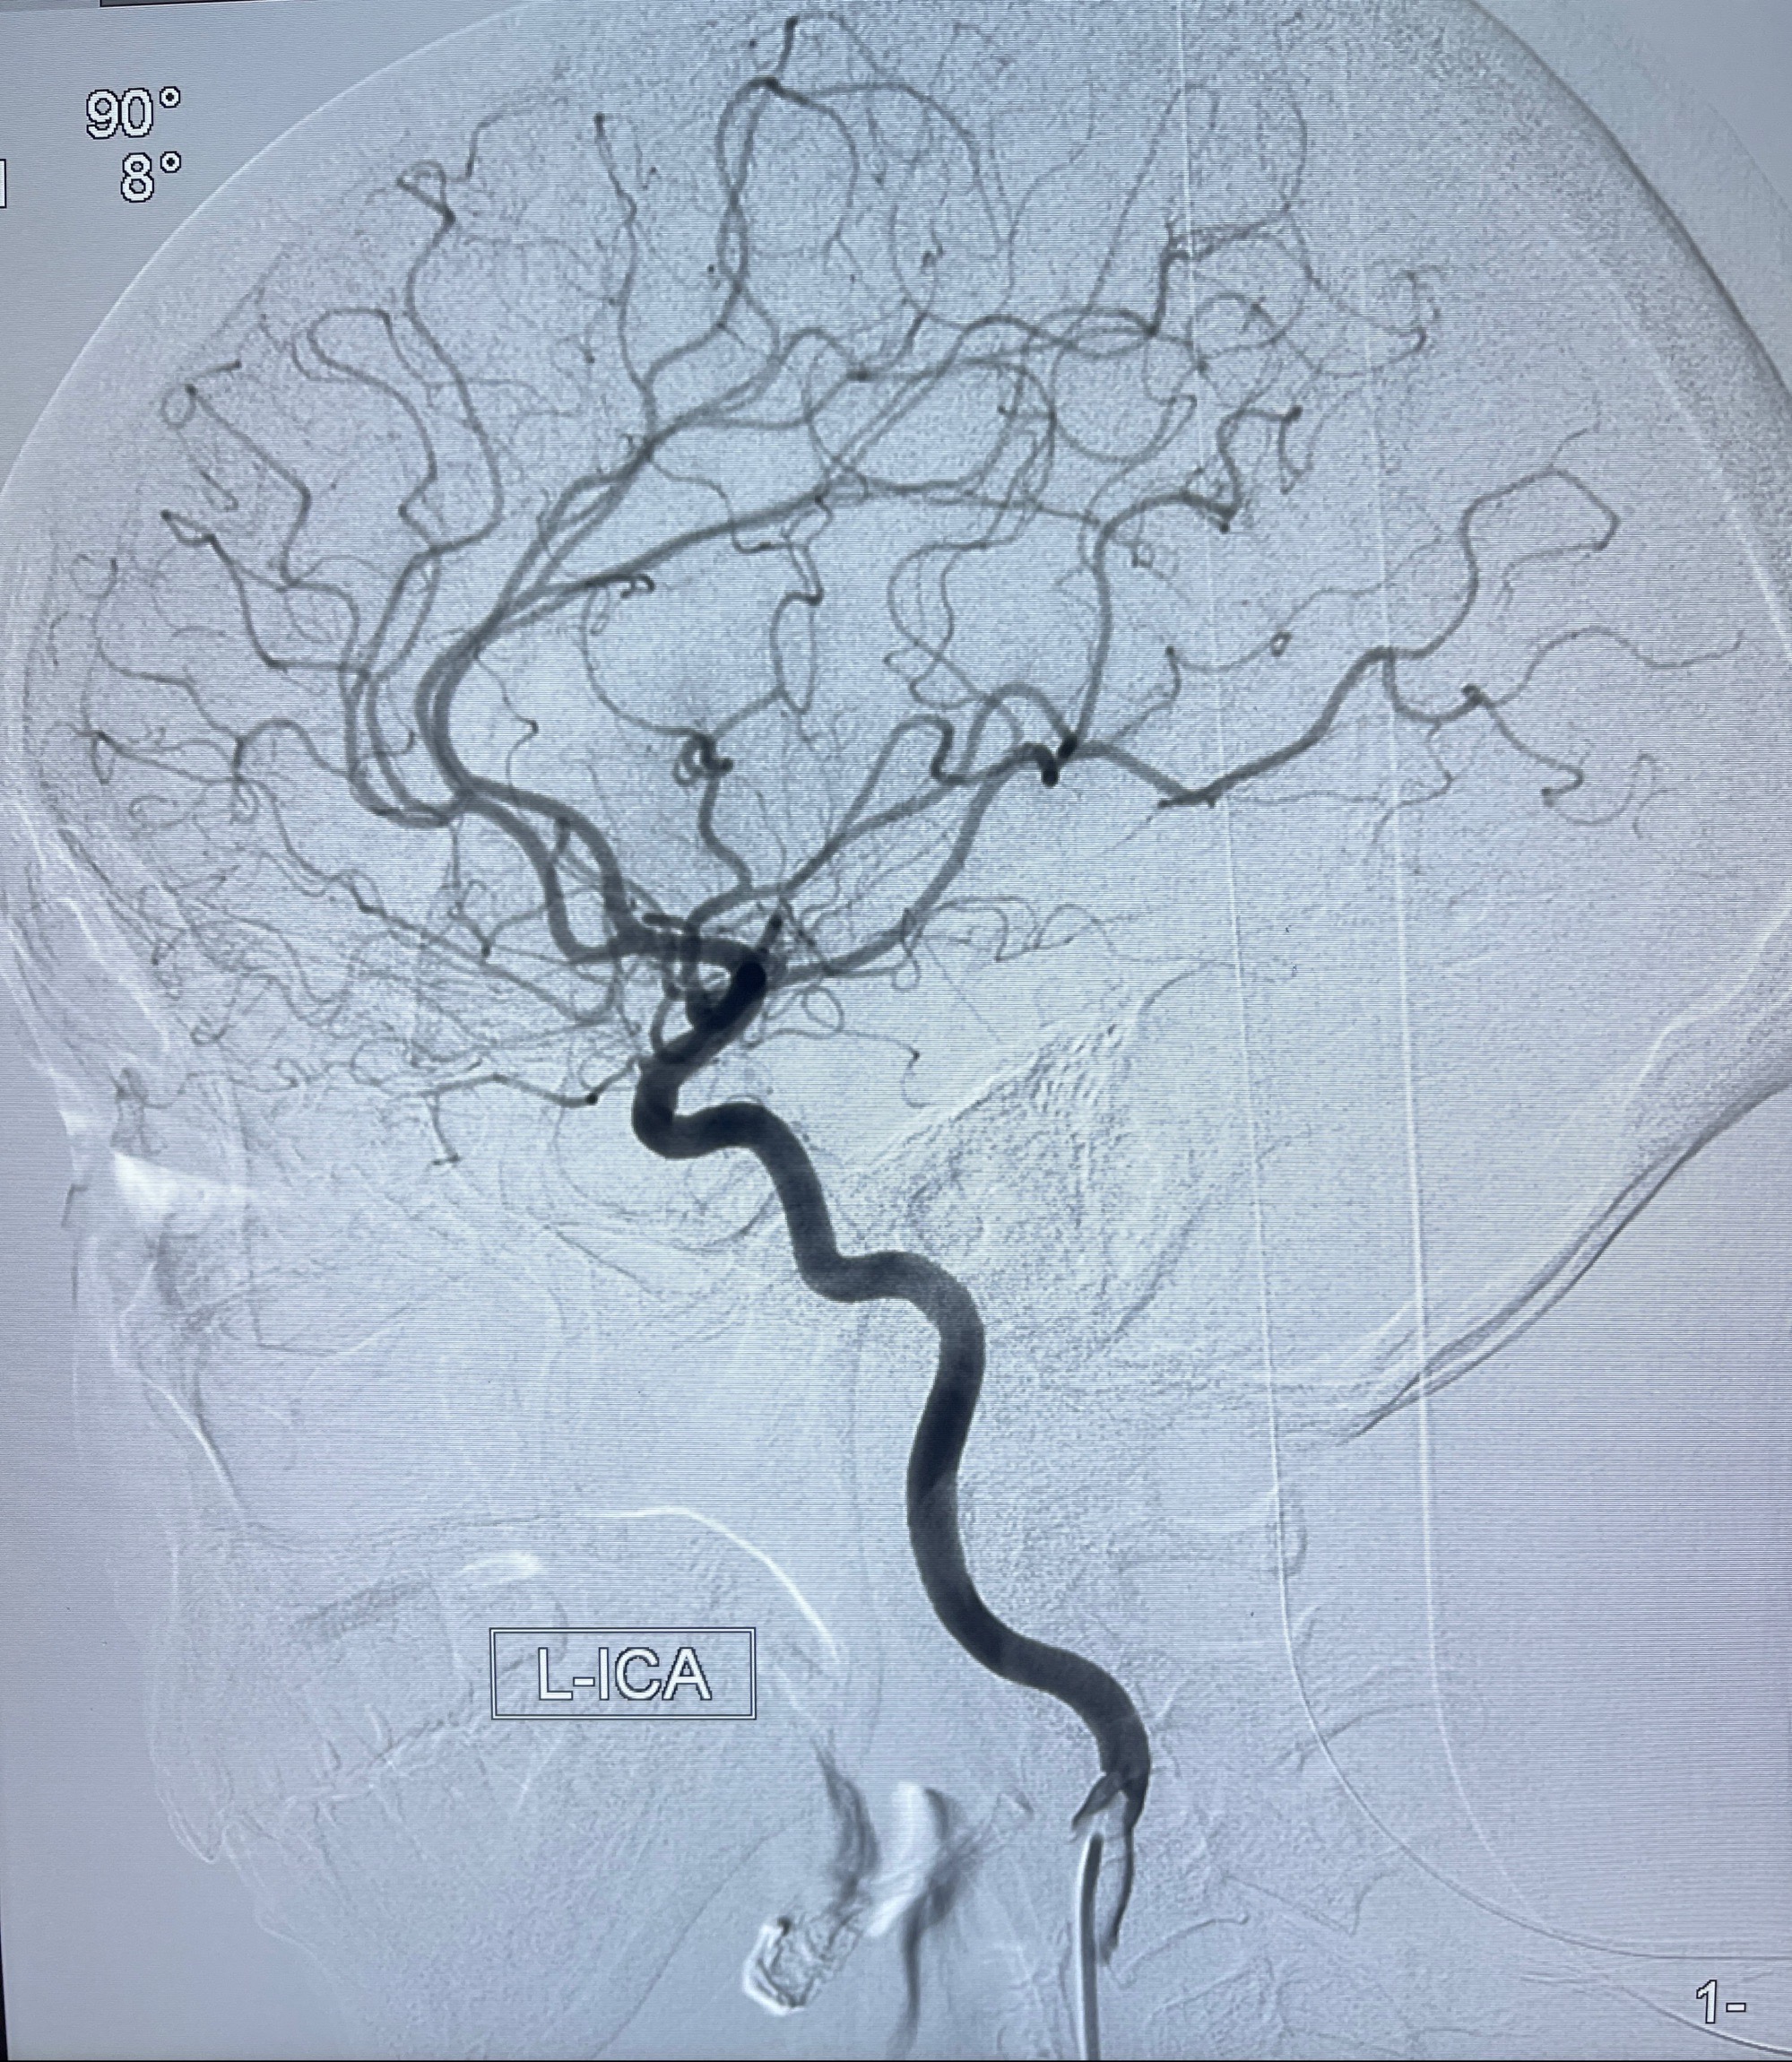

2023-08-14DSA:

左侧大脑中动脉动脉瘤,约2.6-2.8-3.4-2mm大小(瘤颈部、瘤体部、瘤高)